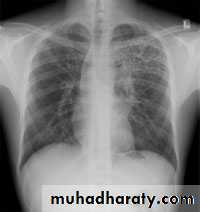

NORMAL PA view